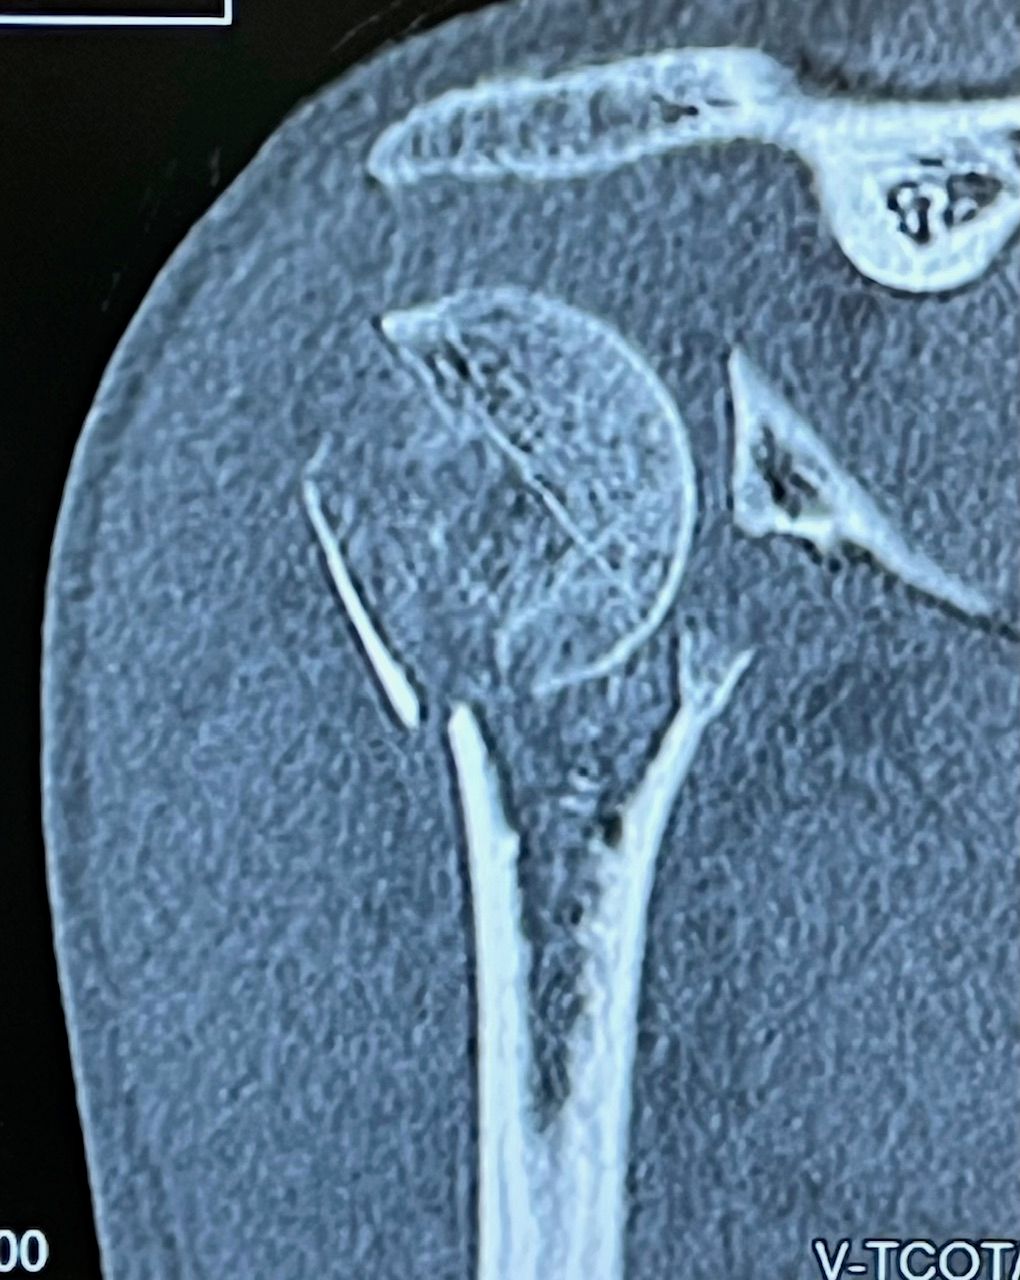

Fotos y vídeos